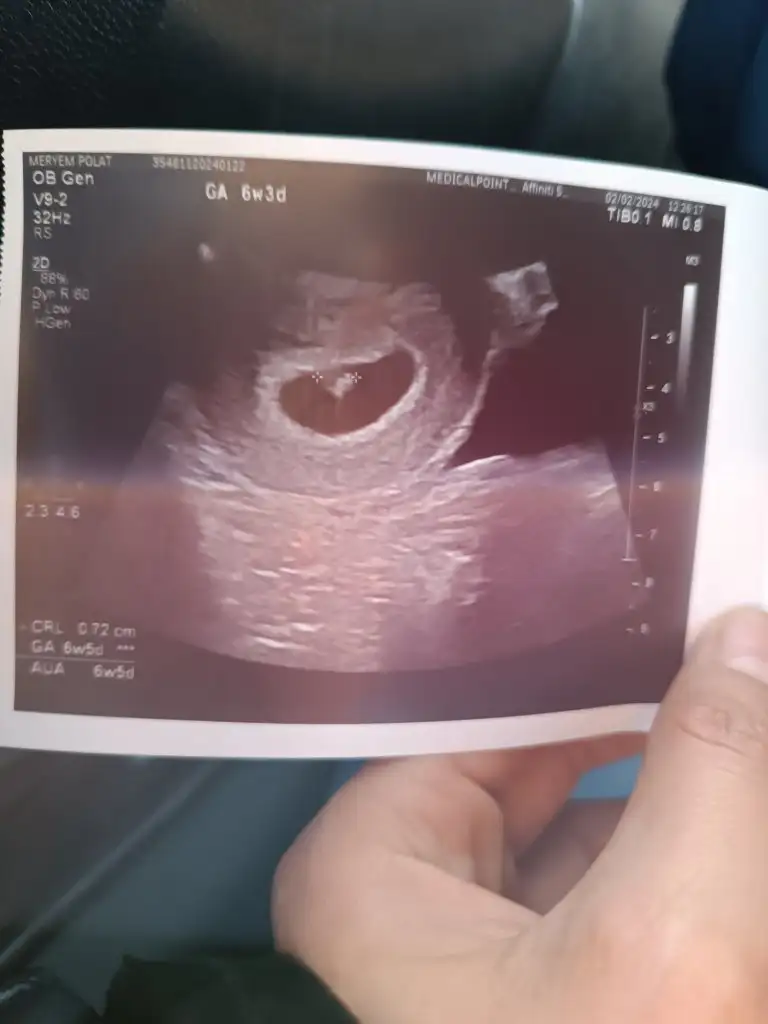

Canım kalp atışı 140 altıya erkek deniyor sana kaç dendiLinakiz normalde 6+4 du ultrason görüntüsüne göre 6+5 haftalık kalp atışını duyduk çok şükür kızlar keseye göre tahmin yapanlariniz varsa bakabilir misiniz

Senin de sanki 120 mi yazıyor bpm denen kalp atışı sayısı demek bana da 114 demişti 2 gün önce canım bakalım tutacak mıLinakiz normalde 6+4 du ultrason görüntüsüne göre 6+5 haftalık kalp atışını duyduk çok şükür kızlar keseye göre tahmin yapanlariniz varsa bakabilir misiniz